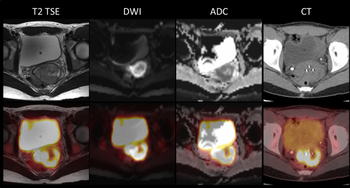

Washington University’s Mallinckrodt Institute of Radiology is imaging cervical cancer patients with hybrid PET/MR. Here’s what they’ve learned about this new modality.